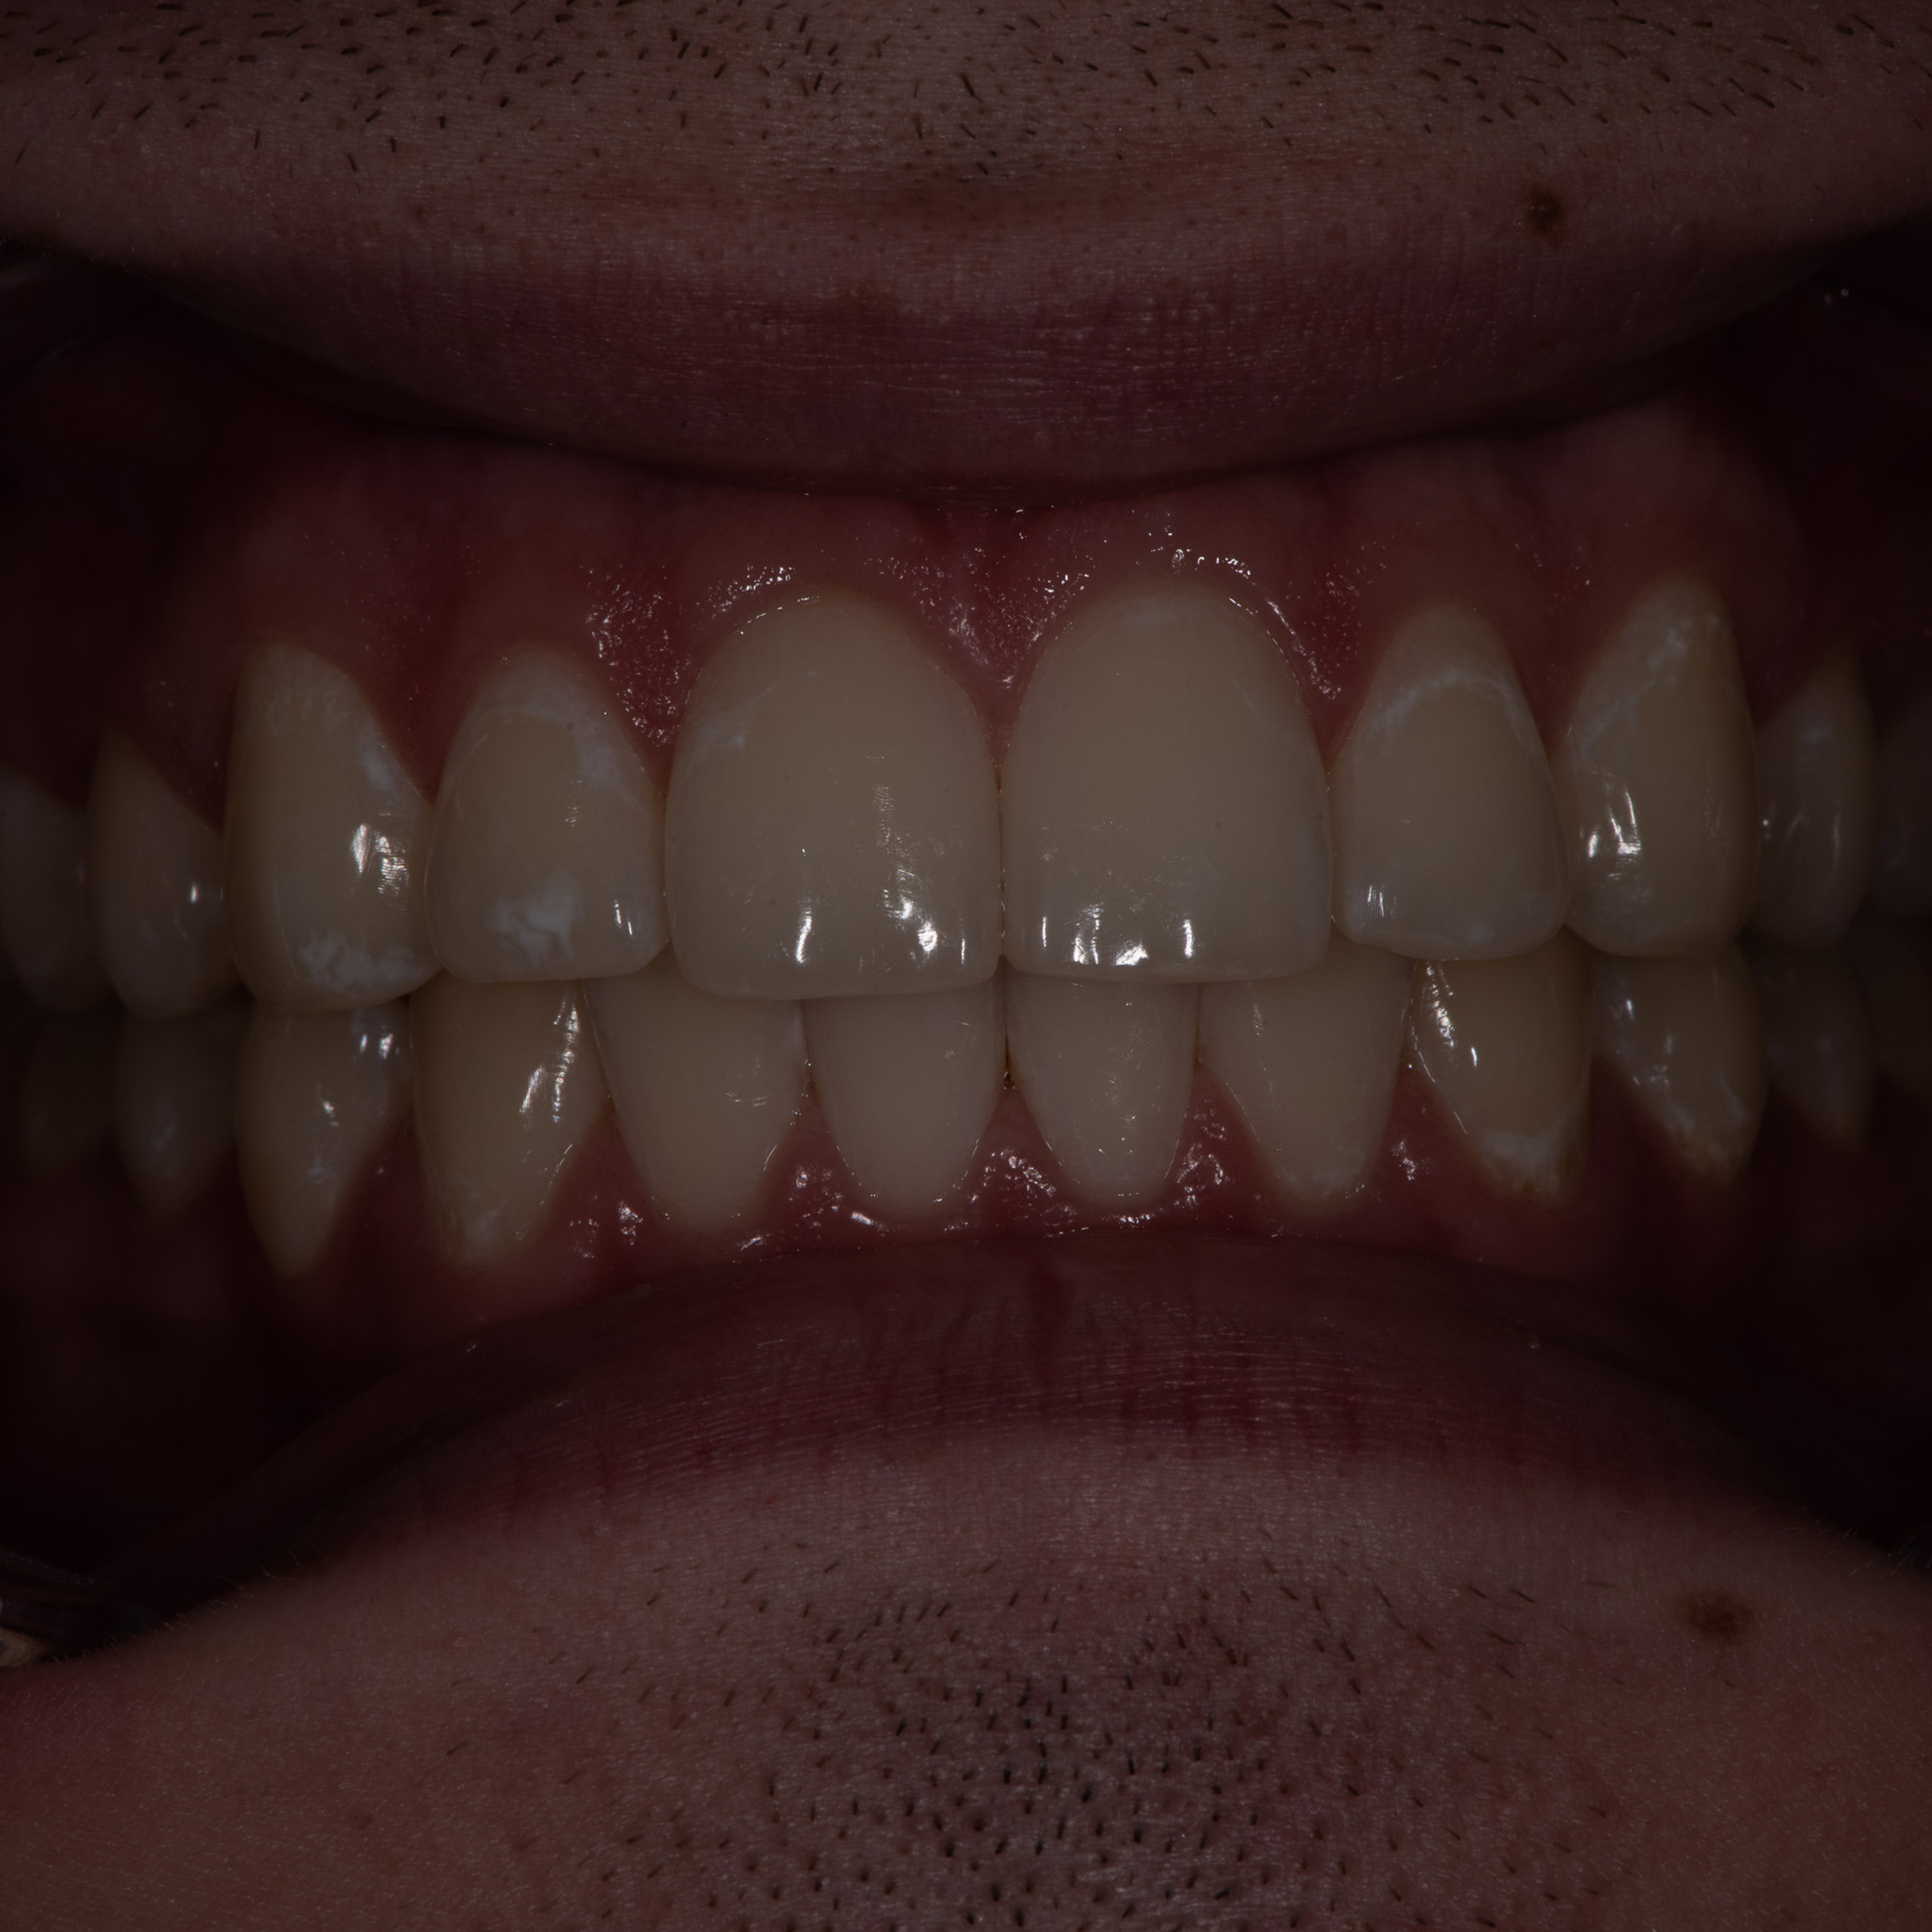

Фотографии учеников до обучения

Фотографии после обучения